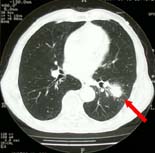

ヘリカルCTにより、3〜5mmの肺がんも発見しています。 肺がんは、CTでなければ、小さいがんは発見しにくいので、 特に、喫煙者には必ずCT検査を勧めます。 |